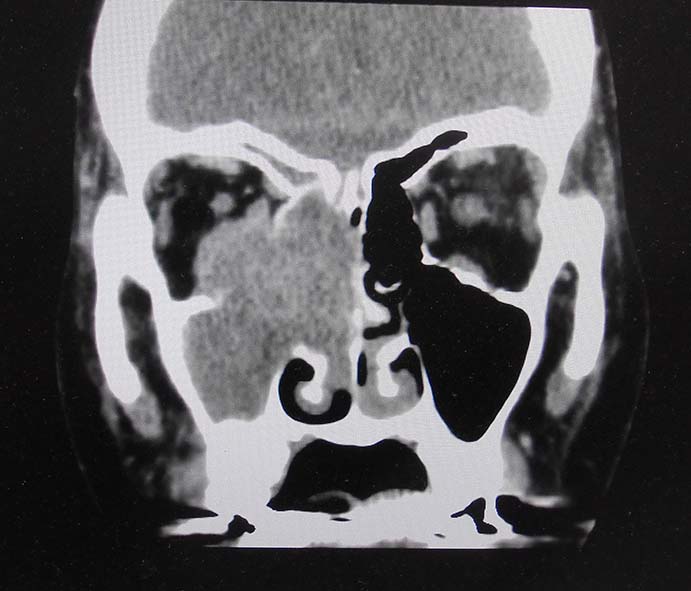

CT所見

副鼻腔腫瘤生検組織